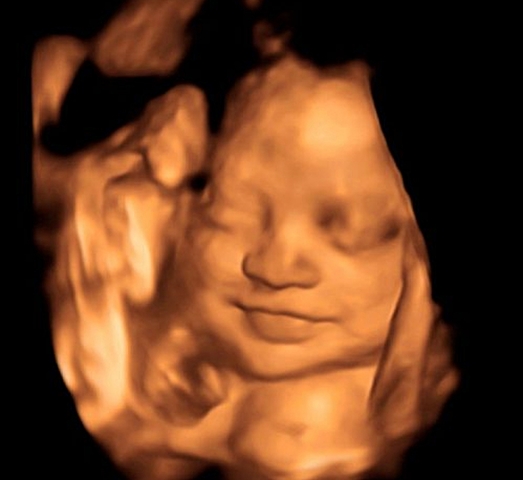

Jan Tesarik introduced the " Virtual Ultrasound Hysteroscopy" to detect ,in 3 dimensions , abnormalities of the uterine cavity without entering the matrix https://youtu.be/i45Prrni5-Y